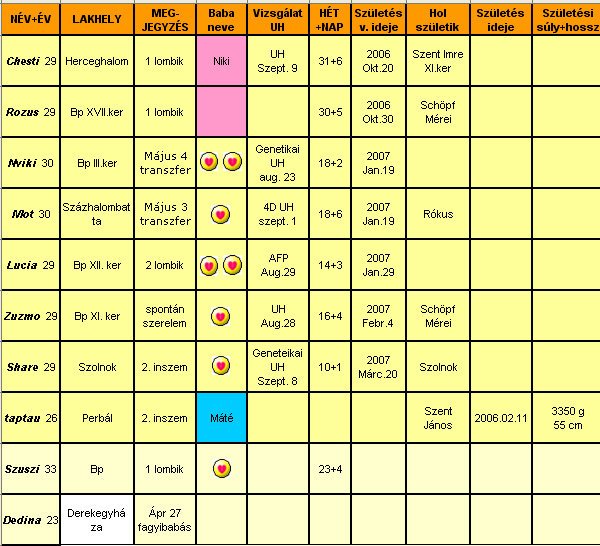

Sziasztok!

Chesti, vettetek már babakocsit? Még mindig akciósnak láttam azt a Pierre Cardint, amiről beszéltél.

Zuzmo, csodálatos élmény lehetett az UH.

Kicsit irígy-irígy.... Meddig dolgozol még?

Rozus, nagyon jók a képek.

Nevetek van már? (lehet, lemaradtam róla)

Viki, le a kalappal, hogy eddig bírtad. Most már tessék sokat pihenni. Brendonban nézelődni jó, és ötleteket szerezni.

Aztán máshol megveszed olcsóbban, vagy elkészítitek saját kezűleg (pl. ágynemű, baldachin, falvédő, stb.).

Lucia, örülök, hogy róka koma elpártolt tőled. Véredet rendszeresen nézik? Ugye neked csak fekvéskor kell majd véralvadásgátlót használnod?

Taptau, jó tanácsokat írsz, mint tapasztalt anyuka. Örülök neki. Homeopátia ügyben, lehet zaklatni foglak. Érdekel a téma, és szeretnék személyes benyomásokról hallani.

Lányok-fiúk, annyira szuper eredmények születnek. Ebből is látszik, hogy a mesterséges megtermékenyítés nem jelenti azt, hogy valami nem stimmel a gyerekkel, más lenne. Sajnos az a tapasztalatom, hogy, ha szóba kerül az inszem-lombik, az emberek a nagy tudatlanságban sok hülyeséget képesek gondolni. És hiába magyaráznám el, nem is hallgatják meg. Rossz sztereotípiák, nem is akarnak tudni arról, hogy másképp is lehet. Nem szeretnék általánosítani, de a többség sajnos ilyen (még szomorúbb, hogy tanult, intelligens embertársaink is kőkeményen tartják magukat ahhoz, hogy lombikkal "hülyegyerekek" születnek - bocsi, nem én mondtam). Saját családi példa, amikor úgy döntöttünk, nem mondjuk, hogy a inszemmel fogant (ha szóba kerül nem tagadjuk, de nem "reklámozzuk). Férjem mamája tudta, hogy szeretnénk már nagyon babát (9 éve vagyunk házasok, ő már akkor dédunokát várt). 1-2 szóval néha elmondtuk, hogy gyógyszert szedek, szurit kapok, később Bp-re járunk orvoshoz. Amikor sikerült, nagyon örült. Láttuk, hogy valamit nagyon akar kérdezni, csak kinyögte, hogy ugye nem lombik volt? Mondtuk hogy nem, hát láttátok volna azt a megkönnyebbülést. Inkább bele sem mentünk az inszembe. Igaz, ő már idős néni, de sajnos a kétgyerekes, okos barátnőm ugyanígy reagált. Ti hogyan látjátok?

Voltam védőnőnél.

Két hét alatt 1,5 kg-ot híztam (a sok sajtos kenyér, amin éltem). Most már oda kell figyelnem, ha nem akarok bálna lenni. Vérnyomásom 90/50. Ne csodálkozzak, hogy szédelgek és húz az ágy. Nem tudom mi legyen, mert rendszeresen kávézni-teázni nem akarok elkezdeni.

Pisilni még mindig 1x kelek fel éjszaka. Ez most akkor sűrűsödni fog?

A legújabb, hogy alul fájdogál a hasam. Nem éles fájdalom, inkább csak érzem. Holnap megyek haematológushoz, lehet, hogy bekönyörgöm magam egy Uh-ra, ha elérem a dokimat. Nem bírom ki jövő hét péntekig.

Na, jó. Kibírom, de nehezen.

Húú, jó sokat írtam. Így jár, aki csavarog.

Csatolok egy képet. Az eddigi szuritermésem. Tegnap leadtam a háziorvosomnak. Benne van a 2. inszemből is 1-2 tű + a véralvadásgátlók.

Szép napot mindenkinek!